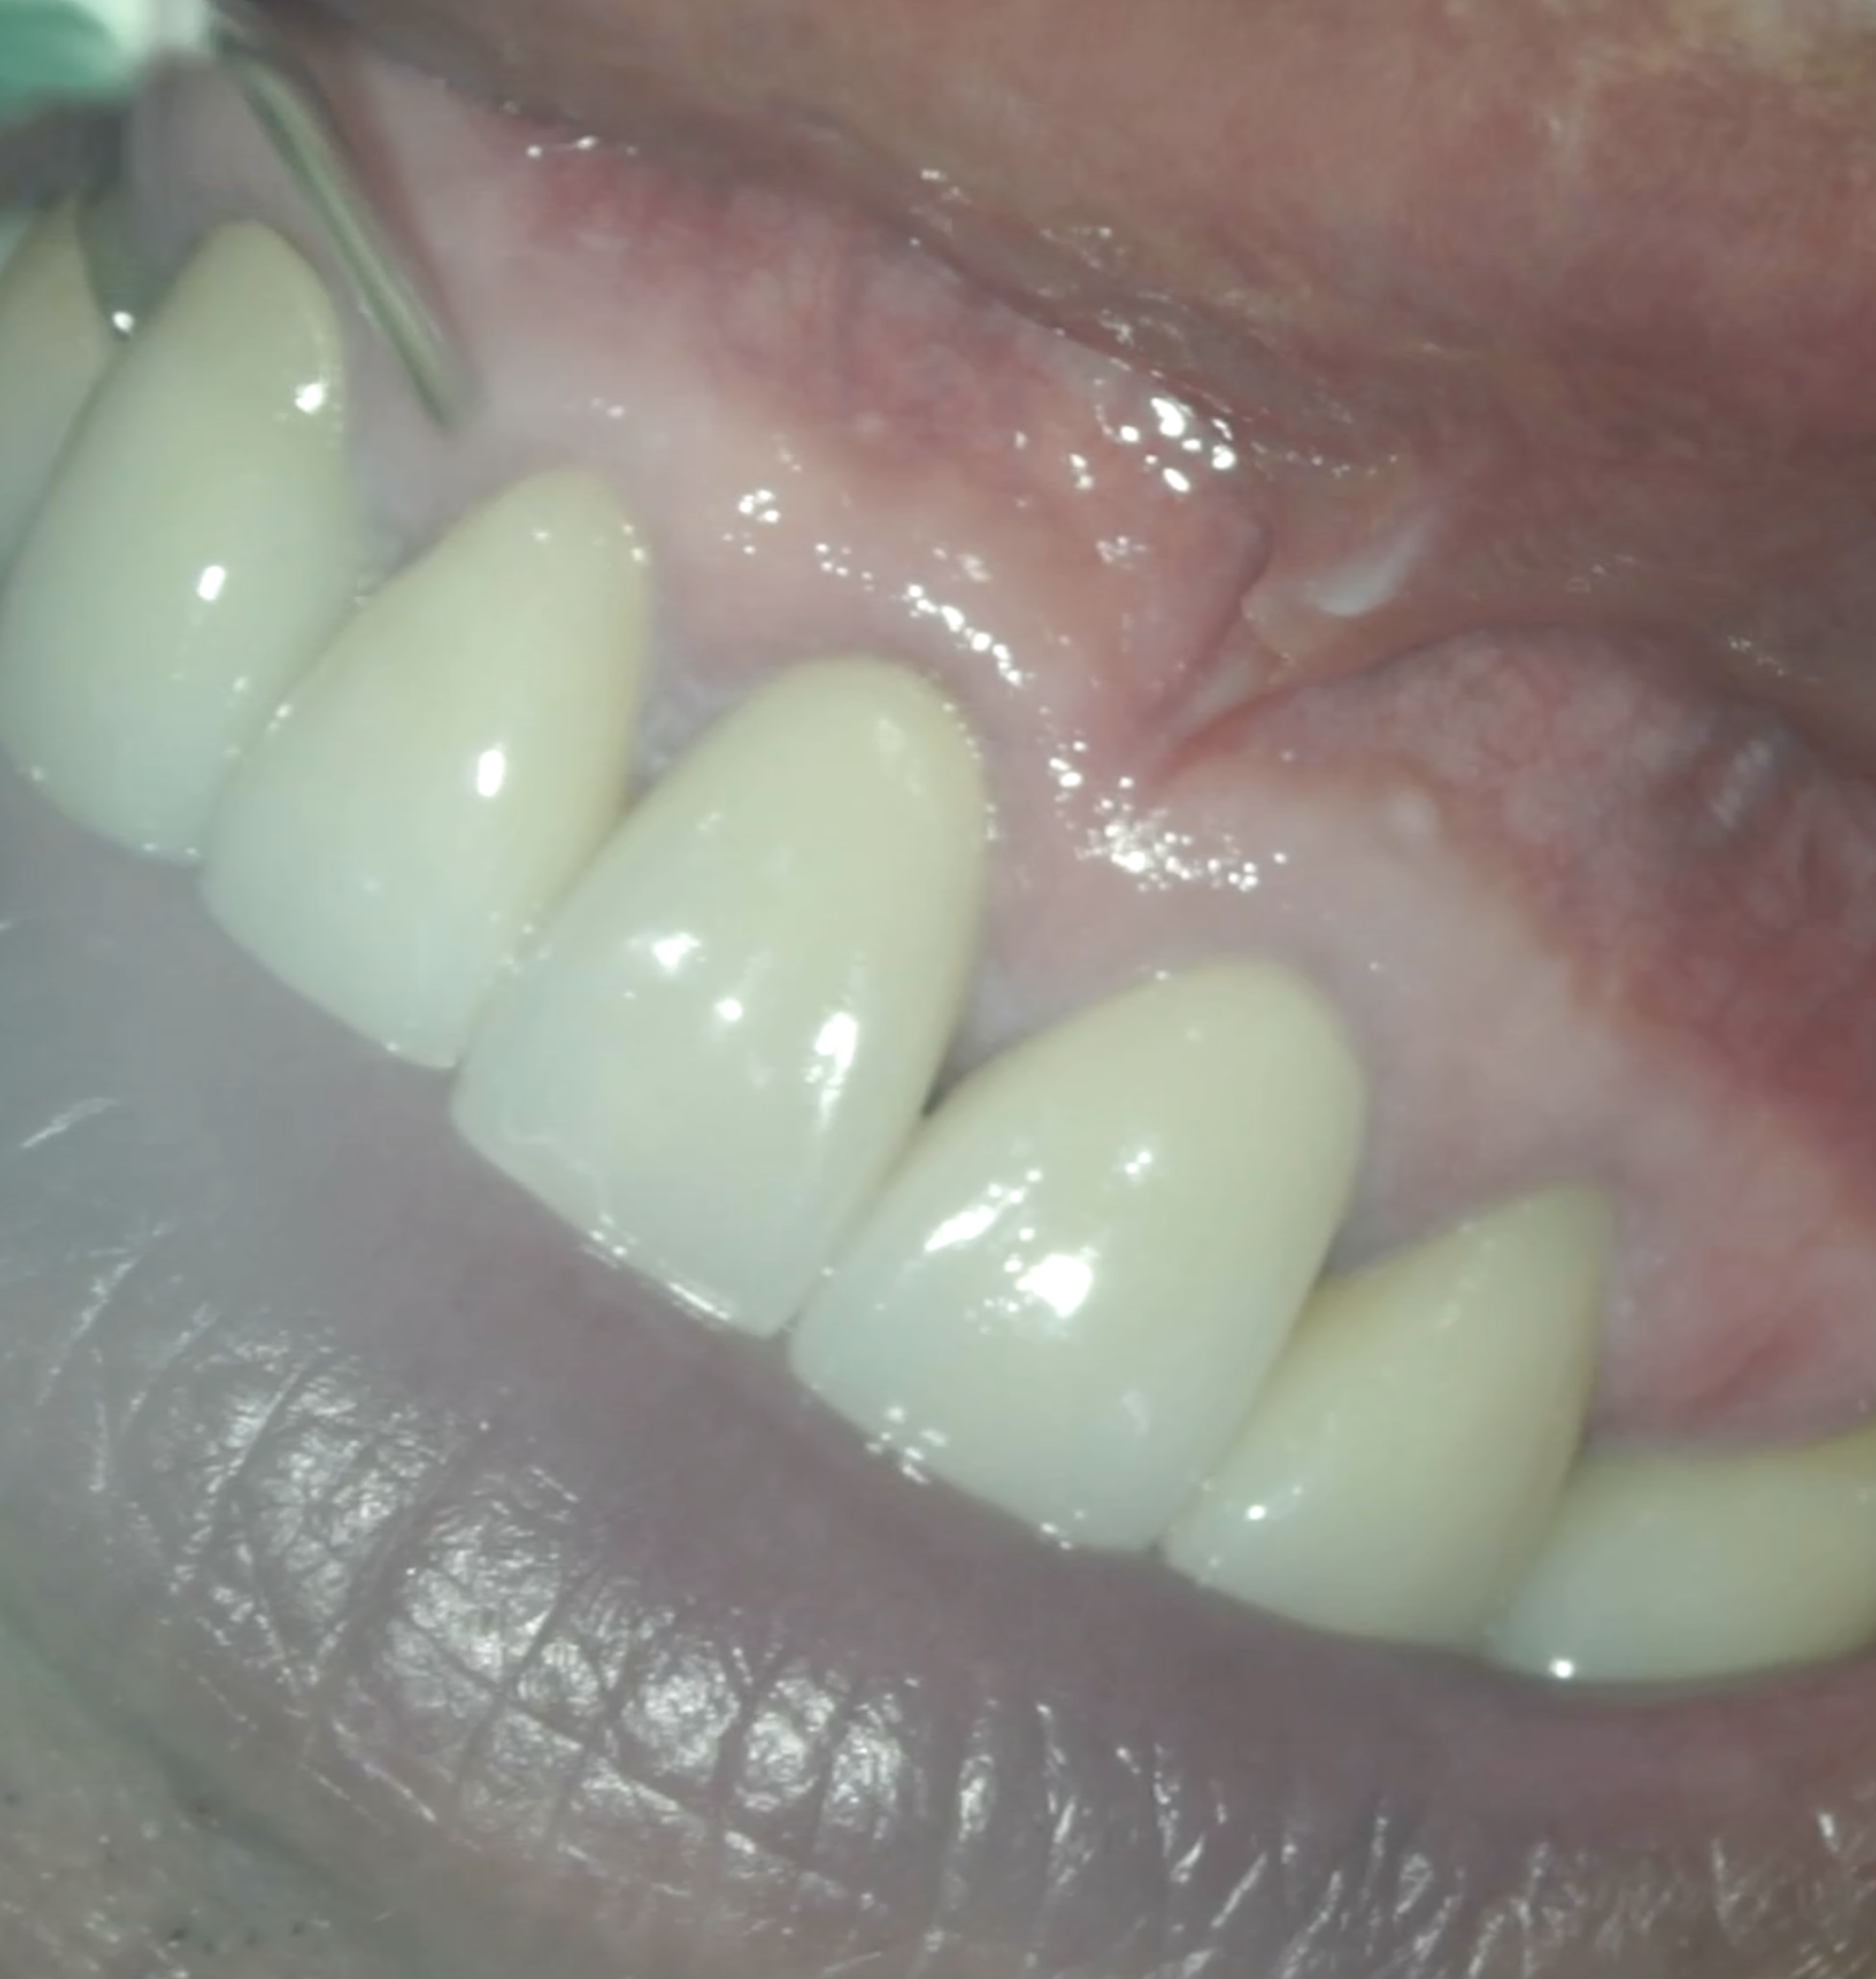

#8,9 Microsurgery 1yr recall(2026.3.11)

#8

初診時と比較した。

問題は大きく解決されている。

初診時のSinus tract, 臨床症状は消失した。